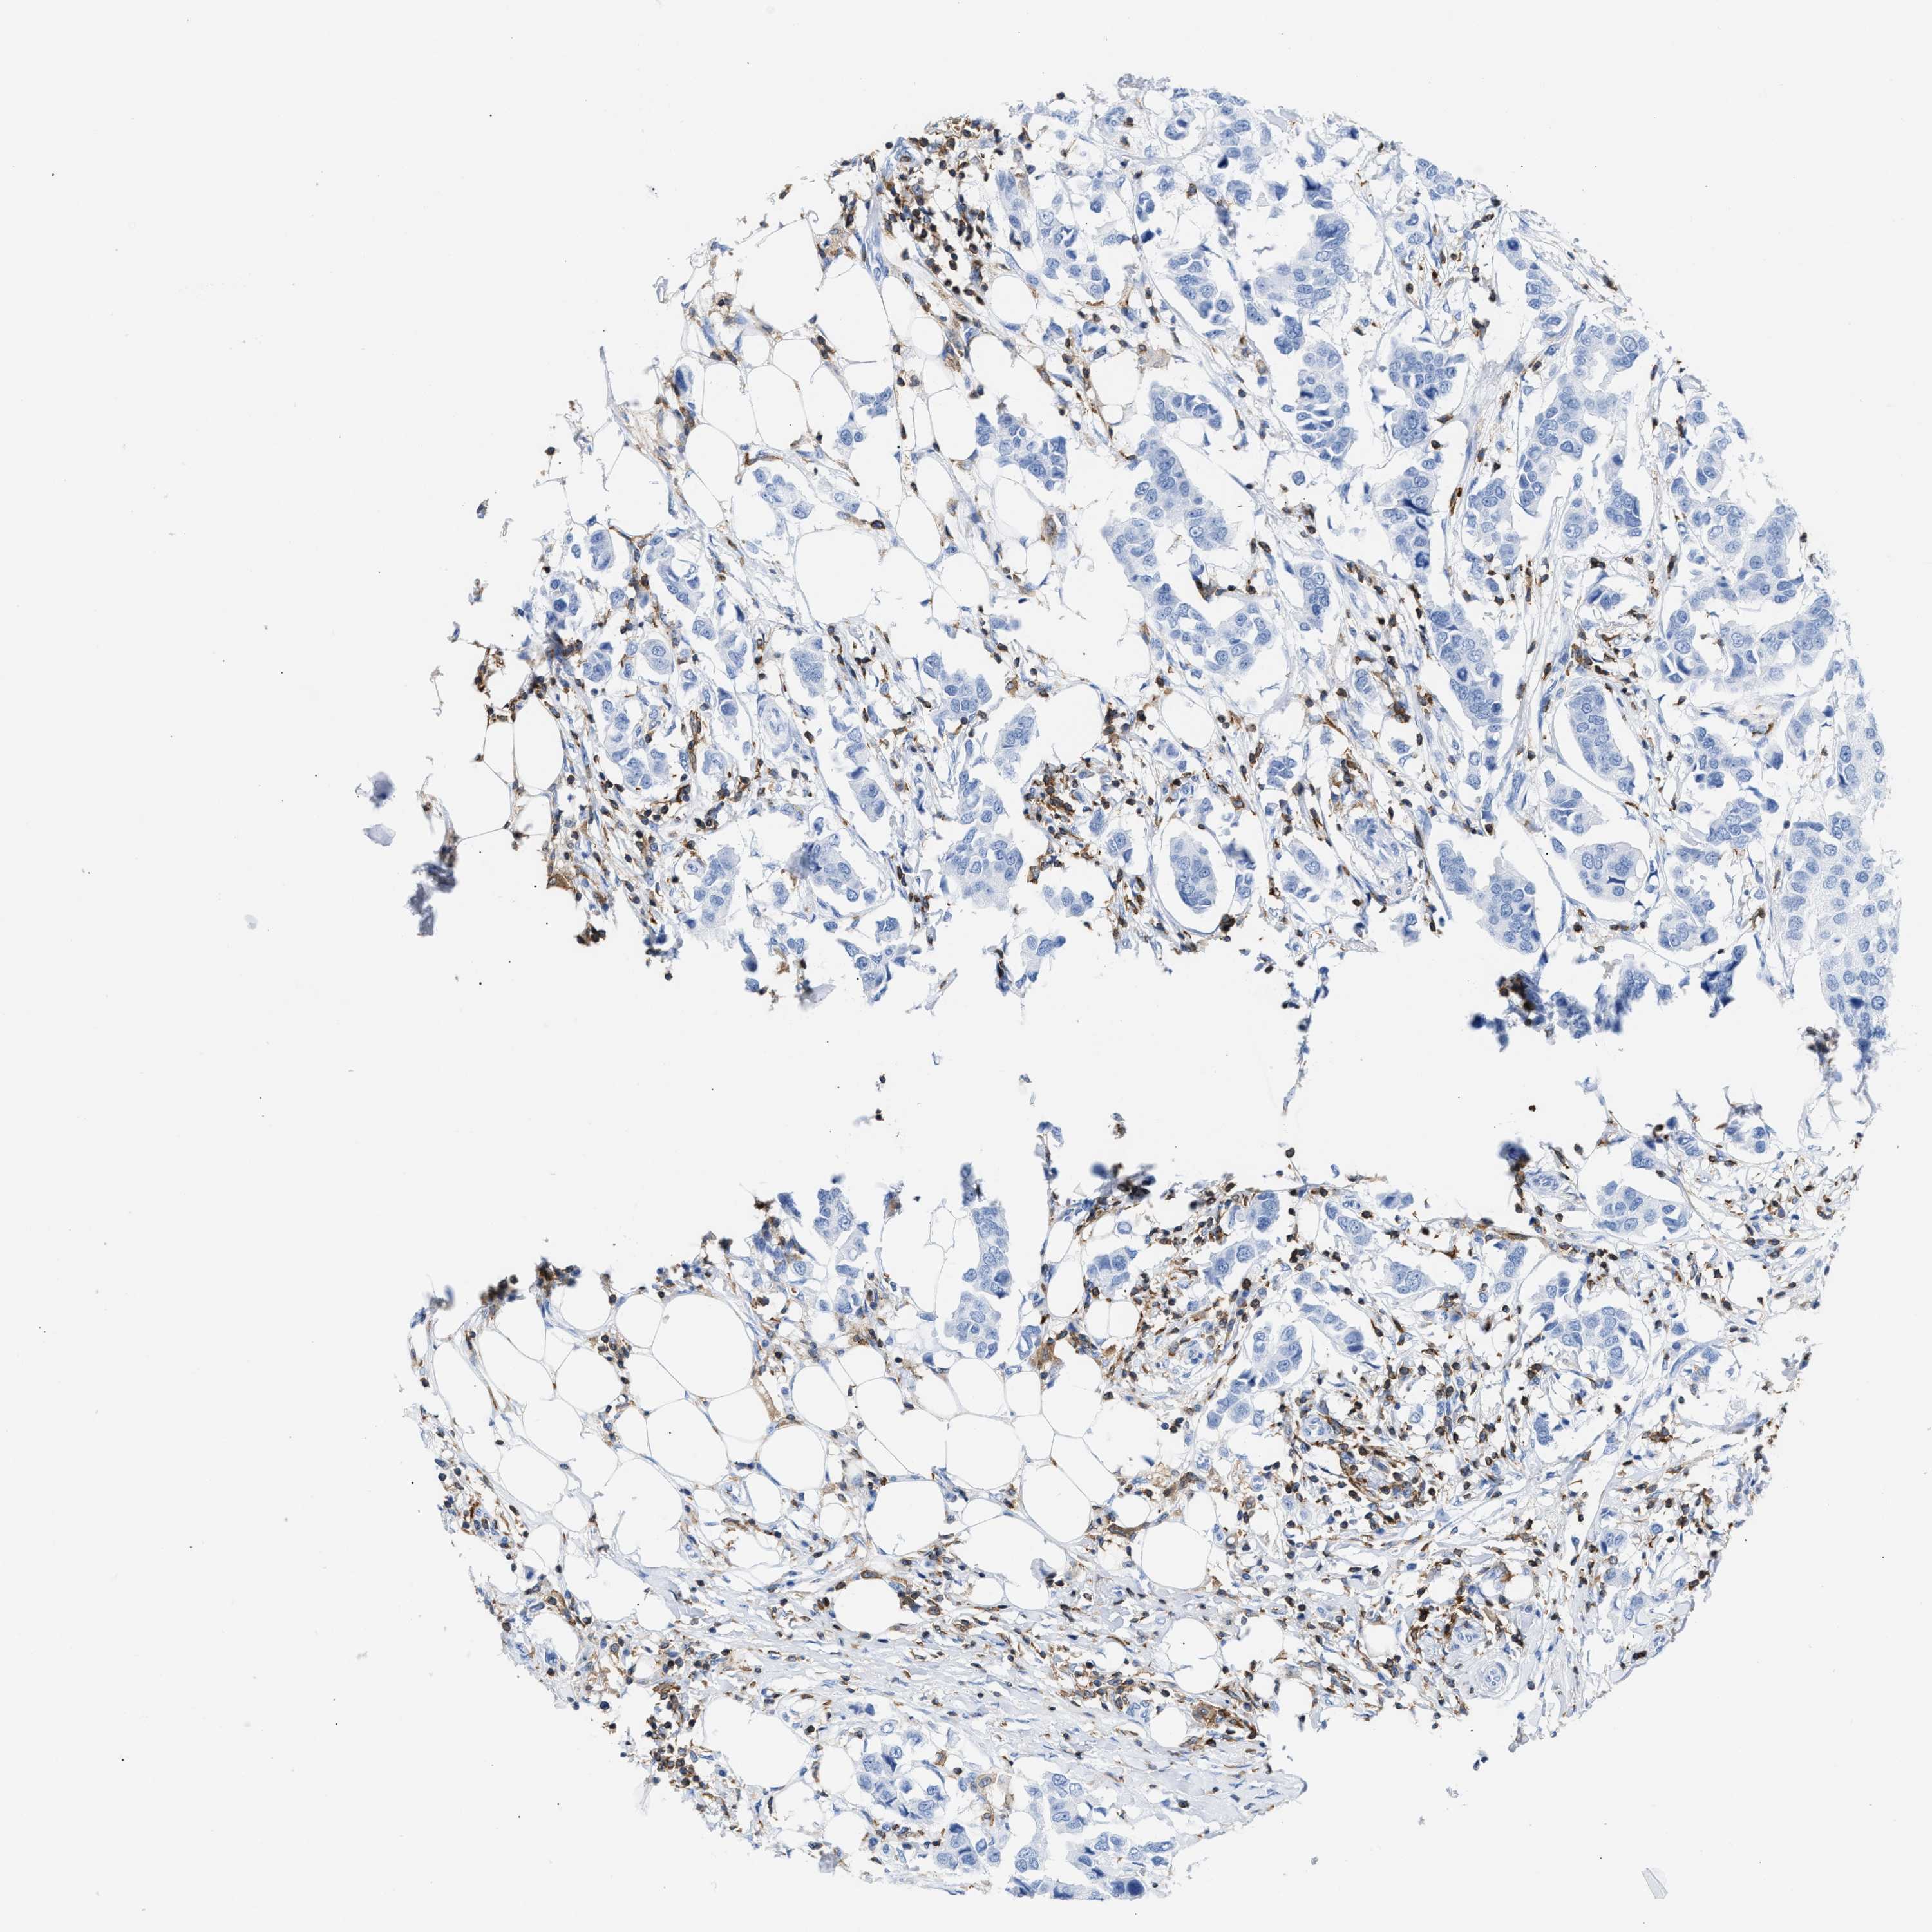

CANCER BREAST CANCER Show tissue menu

BRCA TCGA BRCA VALIDATION PROTEIN EXPRESSION

ANTIBODIES

AND

VALIDATION